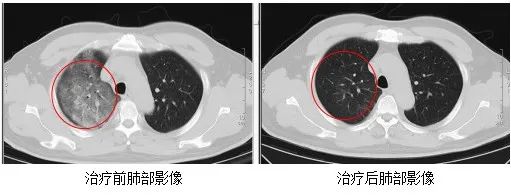

在感染科医护团队的精心治疗与细致护理下,顾先生的发热、咳嗽、胸闷等症状逐渐缓解。复查的CT结果显示,肺部炎症情况得到了明显的改善。目前,顾先生已经顺利康复出院。